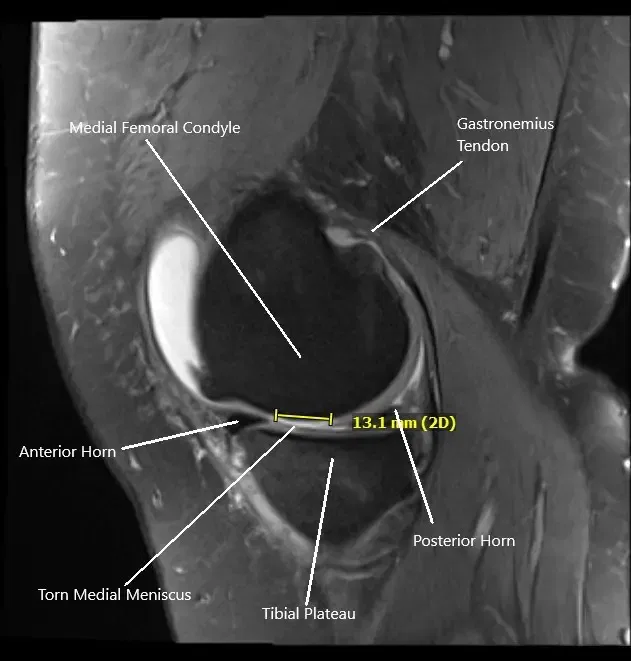

MRI of the right knee in sagittal section showing tear of the medial meniscus

MRI of the right knee suggested a complex tear of the posterior horn of the medial meniscus, tibial subchondral stress fracture, and severe patellofemoral arthrosis. Due to the failure of the conservative management, the patient was advised surgical management. Risks, benefits, and potential complications were all discussed at length with the patient. The patients agreed to go ahead with the procedure.